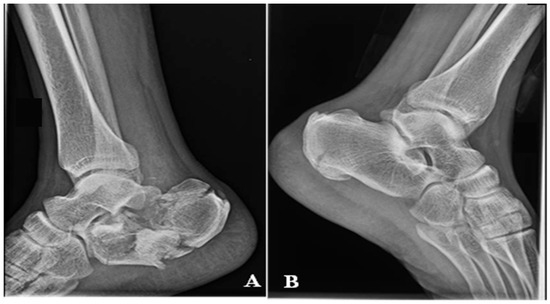

Background: Covering the defects around the calcaneus is still a largely debatable subject. In the classical view, the defects at the level of the foot can be treated only by a free flap. In a modern approach, it has been observed that for small or m...